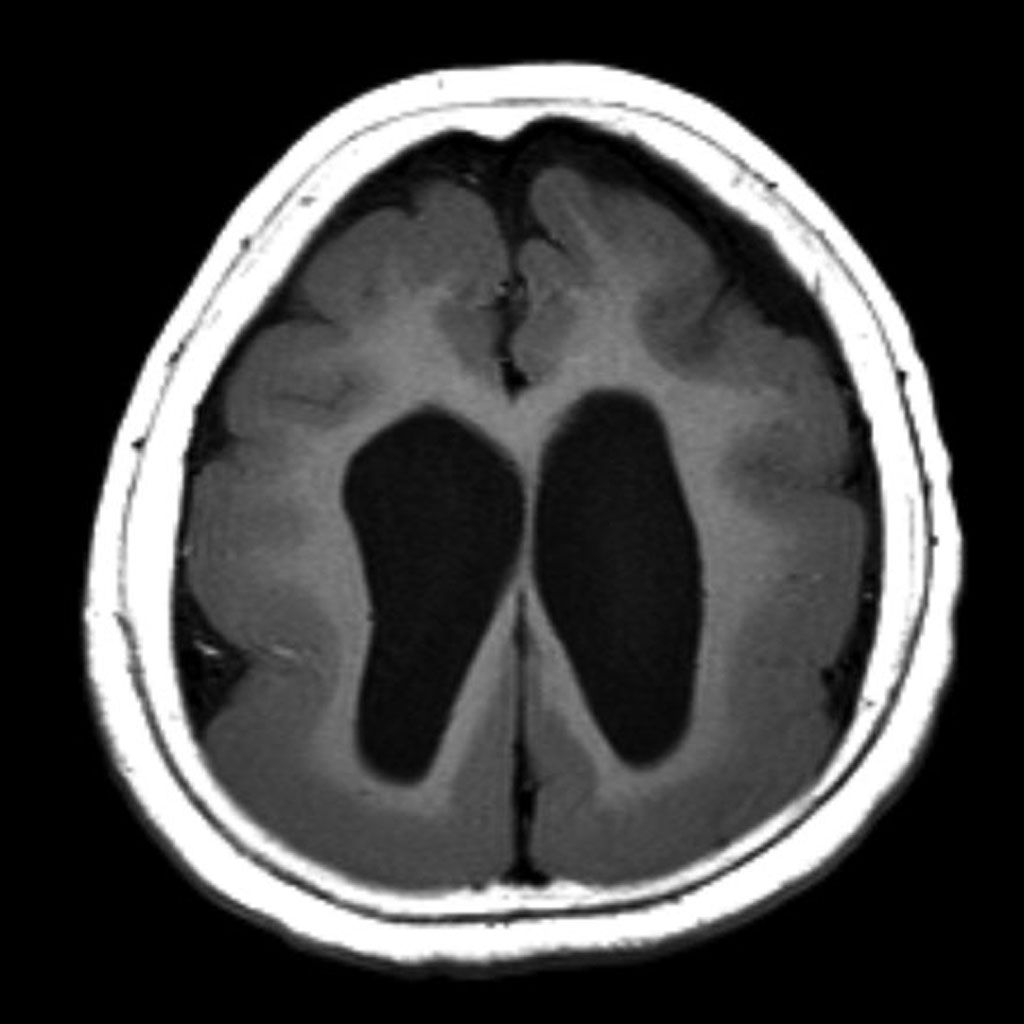

巨脑回畸形【西安高尚医学影像病例】

巨脑回畸形